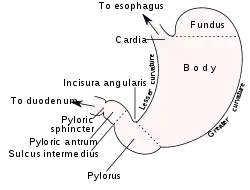

| Outline of stomach, showing its anatomical landmarks, including the pylorus. | |

Pyloric stenosis is a narrowing of the opening from the stomach to the first part of the small intestine (the pylorus).[1] Symptoms include projectile vomiting without the presence of bile.[1] This most often occurs after the baby is fed.[1] The typical age that symptoms become obvious is two to twelve weeks old.[1]

The gastric outlet obstruction due to the hypertrophic pylorus impairs emptying of gastric contents into the duodenum. As a consequence, all ingested food and gastric secretions can only exit via vomiting, which can be of a projectile nature. While the exact cause of the hypertrophy remains unknown, one study suggested that neonatal hyperacidity may be involved in the pathogenesis.[10] This physiological explanation for the development of clinical pyloric stenosis at around 4 weeks and its spontaneous long term cure without surgery if treated conservatively, has recently been further reviewed.[11]

Diagnosis is via a careful history and physical examination, often supplemented by radiographic imaging studies. Pyloric stenosis should be suspected in any infant with severe vomiting. On physical exam, palpation of the abdomen may reveal a mass in the epigastrium. This mass, which consists of the enlarged pylorus, is referred to as the 'olive',[14] and is sometimes evident after the infant is given formula to drink. Rarely, there are peristaltic waves that may be felt or seen (video on NEJM) due to the stomach trying to force its contents past the narrowed pyloric outlet.